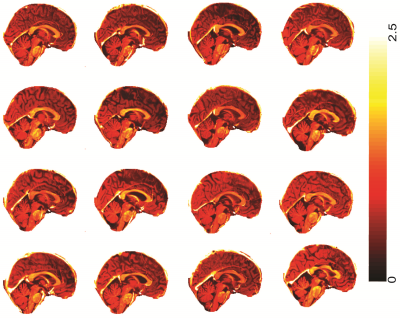

Fig 3 Shows increased myelination in saggital sections of sixteen CFS patients (out of forty-five). The white arrows arrow indicates the higher degree of myelination in CFS patients in-comparison to the healthy controls

Fig 4 Shows degree of myelination in saggital section of sixteen normal controls (out of twenty-seven). A lower degree of myelination in the brain stem and corpus callosum was observed compared to CFS patients.